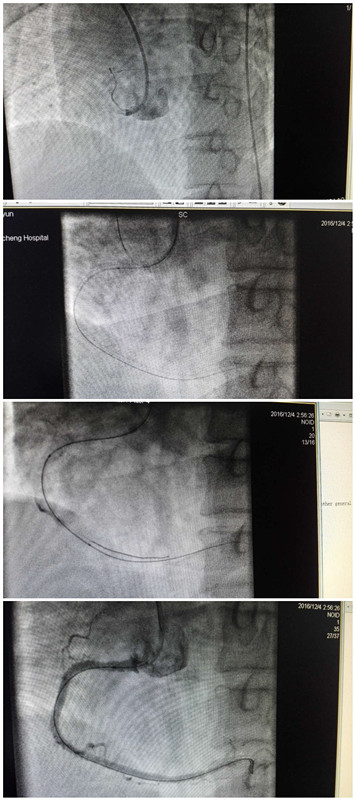

患者为52岁的男性,因持续心前区疼痛6小时就诊于我院急诊科,据心电图特点诊断急性下壁心肌梗死,于12月4日凌晨收住心血管一病区、神经内科。薛虹主任迅速赶到科室,询问病情检查患者后,意识到必须尽快行冠脉介入治疗开通闭塞血管,挽救心肌,使患者得到最大的获益。与家属多次沟通,家属经过紧张的心理调节后,同意手术开通血管。向总值班闫副院长、蔡护士长汇报后,得到了大力支持。紧张术前准备的同时,通知介入室做好手术准备,科室李金科主治医师第一时间从咸阳赶到,介入室人员、麻醉师、省人民医院心内科梁磊副主任迅速到位,一切准备就绪,于凌晨2点55分开始手术,术中发现右冠开口齐头闭塞并有夹层,前降支中段60%狭窄,远端闭塞,第一对角支90%狭窄,眼前的情景让术者震惊了,比预想的要严重得多,术中随时可能室颤,心脏骤停,医生要冒极大的风险,如不开通血管,则死亡一步步逼近。手术面临着艰难的选择,生死关头,责任和担当是相等的沉重,需要果断决策,医者仁心,为救患者,甘当风险,一场没有硝烟的战斗开始了,手术中的每一步都是难点,需要耐心细致、精确地操作,通过艰难的跋涉,最终开通了右冠脉,植入了3枚支架,再次造影显示血管开通血流TIMI3级,手术取得了圆满成功,时间已是凌晨5点多了。大家都如释重负,脸上露出了胜利的喜悦,沉重的铅衣及2个多小时紧张的手术使大家筋疲力尽,汗流浃背。

这是一台高质量、高风险的手术。患者冠脉造影结果显示:右冠脉口齐头闭塞并可见夹层,且为多支病变。右冠脉为本次发病的“罪犯”血管,表明本次发病为右冠脉慢性严重狭窄基础上急性闭塞,慢性病变血管多伴严重钙化,血管僵硬,加至右冠脉开口处病变,在立体位很难寻找到真正开口,能否将导丝成功送入对术者是一个挑战,术中稍有不慎,可能导致夹层扩大,若导丝送入假腔内,造成不可预想的后果,若导丝刺破血管出现心包填塞;用球囊扩张弥漫病变的血管时,势必造成病变处血管壁损伤,斑块破裂出现新的夹层和血肿,导致无前向血流,若扩张不充分,将会使支架不能顺利到达病变部位,严重时还可能导致支架脱载,造成灾难性后果。而且右冠脉闭塞多伴有心动过缓、低血压,随时会出现休克、心脏骤停,术中充满着各种危险的玄机,需要术者敢于承担风险,迎难而上,敢于尝试,果断大胆决策,并且具备精良的医术和强大的心理素质来应变术中瞬息万变的情况。